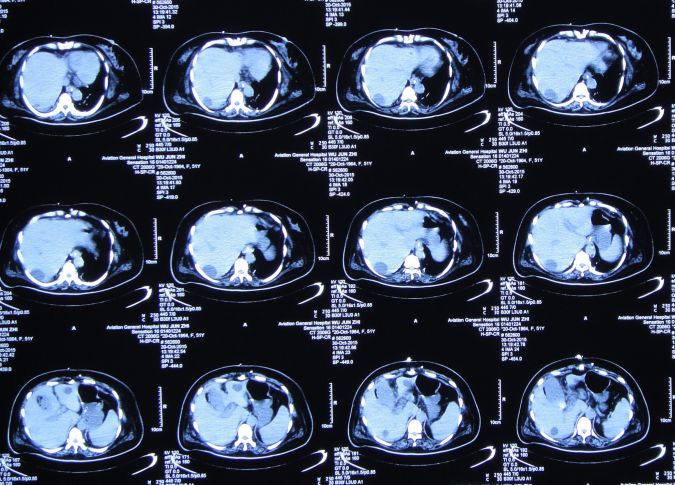

当日上午患者诉上腹部、下胸部疼痛。急查腹部CT:肝内多发囊肿;胆囊结石、胆总管结石(图32)。

图32:2015年10月27日腹部CT肝内多发囊肿;胆囊结石、胆总管结石

ERCP术后第一天即2015年10月30日,患者症状仍无改善,精神差,呼吸急促,喘憋,张口呼吸,言语不清,持续胃肠减压。白细胞:19.3*10^9/L↑,中性细胞比率:94.0%↑,血红蛋白:74g/L↓,血小板:51*10^9/L↓,白蛋白:26.3g/L↓。急查腹部CT:胆囊增大、胆囊结石。

图34:2015年10月30日腹部CT:胆囊增大、胆囊结石

胆囊造瘘术后第3天即2015年11月2日,患者神志朦胧,发热,最高T39.0℃;查胸CT:双肺感染(图36)。查腹部CT:胆囊造瘘术后改变,胆囊较术前缩小,无结石影(图37)。

图37:2015年11月2日腹部CT:胆囊较术前缩小

胆囊造瘘术后第17天即2015年11月16日,患者神清,仍间断呕吐;查腹部CT:与2015年11月2日腹部CT比较:1.胆囊内高密度影消失,壁模糊。2.肝内多发囊肿较前无明显变化。3.腔静脉支架术后改变(图39)。

图39:2015年11月16日查腹部CT

普外科会诊,考虑患者胆囊周围仍有渗出水肿,可能导致消化道梗阻;并进行了胆囊局部松解引流处理,缓解局部压力。查胸CT:肺部感染伴右侧胸腔积液(图40),给予对症处理。

胆囊造瘘术后第56天即2015年12月25日,复查头CT:颅内无异常(图44)。查腹部CT:胆囊造瘘术后,改变(图45)。

图45:2015年12月25日腹部CT:胆囊造瘘后改变

查腹部CT:胆囊切除术后改变,无明显异常(图53)。

图53:2016年1月30日腹部CT:胆囊切除术后改变,无明显异常